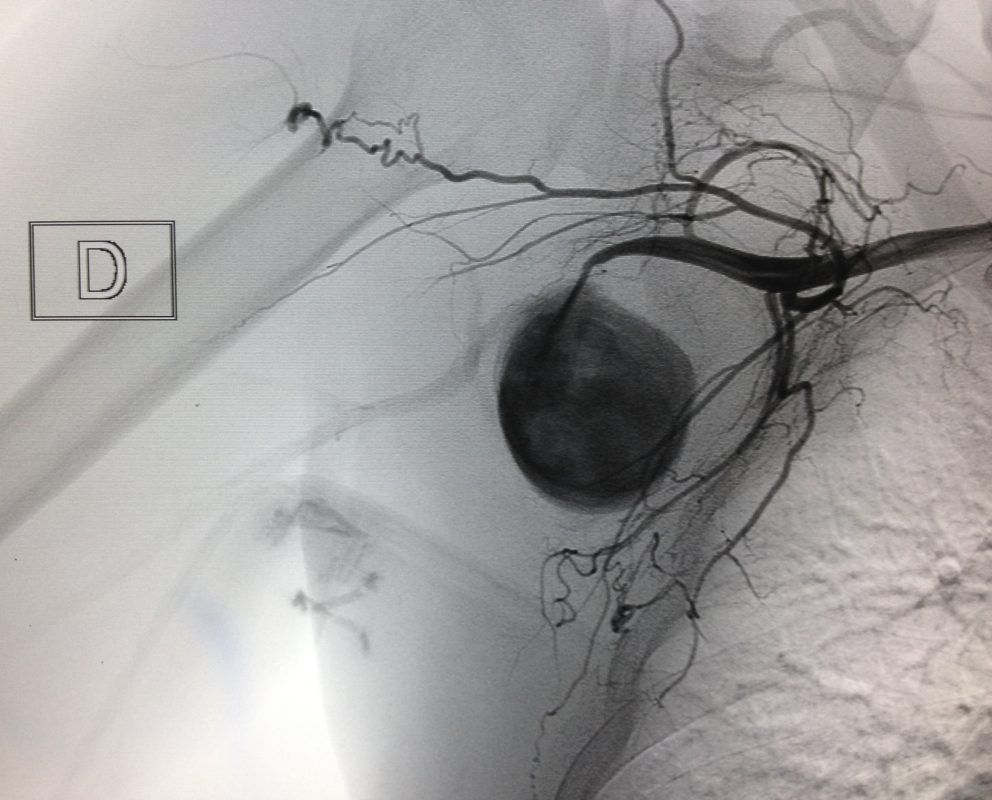

Tratando um volumoso pseudo-aneurisma de artéria axilar direita em paciente vítima de ferimento por arma de fogo no passado recente. O tratamento foi realizado pelo implante de um Viabahn – Stent revestido.